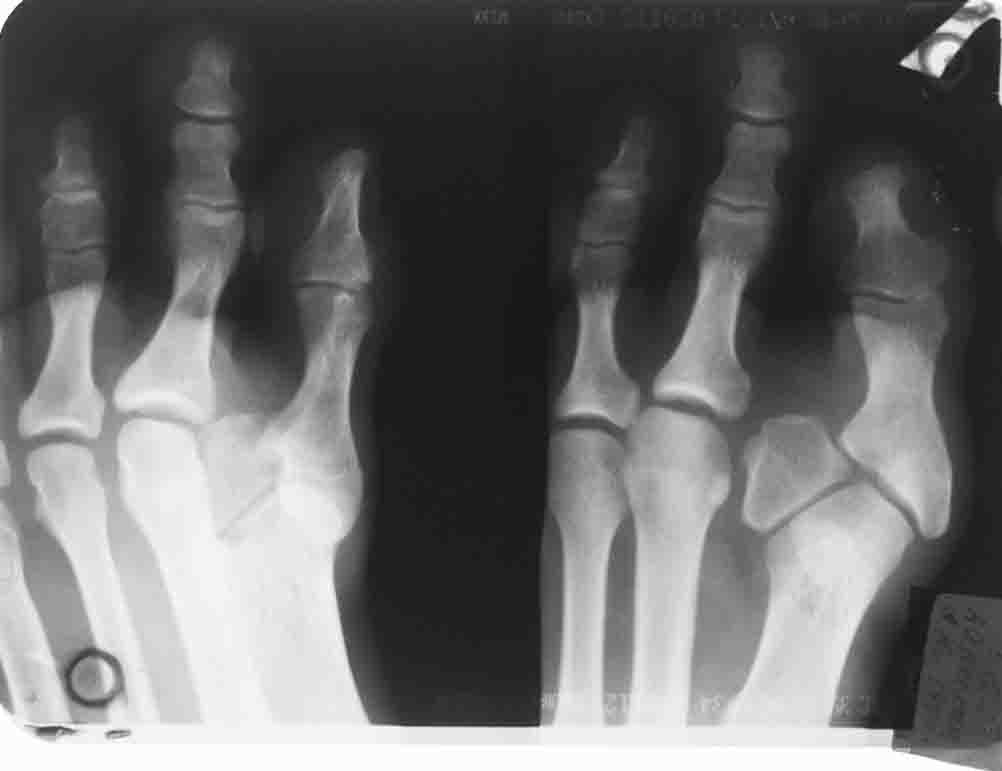

Была выполнена операция. Иссечен свищ. Свищ исходил из дегенеративно измененных тканей капсулы 1 плюснефалангового сустава по всей видимости это возникало из-за натяжения мягких тканей в области аномальной кости. Резецирована кость.

R граммы вышлю. Вопрос об артодезе или артропластике будет обсуждаться после того, как заживет рана и больной походит

Прилагаю послеоперационные рентгенограммы.

Планирнуем использовать приводящуюю шину для 1 п.

Вопрос о проведении реконстрнуктивных операций на костях поднимем при наличии жалоб.